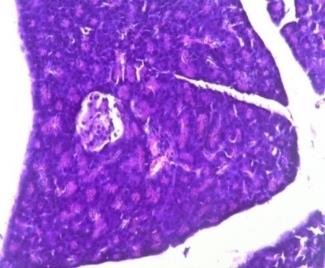

Effect of Hydroalcoholic extract of Linaria ramosissima (Wall.)Janch on pancreas by Histopathology

Fig 3A shows normal islets of langerhans and β cells in pancreas of normal control group.(non-diabetic) In positive control group

(Diabetic) the number of pancreatic islets as well as β-cells is reduced as compared to control group with most of β-cells being destroyed. (Fig 3B) Section of pancreas from groups treated with glibenclamide (Fig 3C) and both doses of test drug (Fig 3D & 3E) showed increase in pancreatic islets & number of β-cells in the pancreas. The damaged β-cell seen after induction of diabetes were no longer observed after treatment with extract. This indicates that the test drug causes regeneration of β-cell of islets of langerhans of pancreas and restores normal cellular appearance and size of islets with hyperplasia.

Fig. 3a: Normal Control (Non-diabetic)

Fig. 3b: Positive Control (Diabetic)

Fig. 3c: Glibenclamide Standred drug (10 mg/kg)

Fig. 3d: Test-1 (Low dose) 200 mg/kg

Fig. 3e: Test-2 (High dose) 400 mg/kg